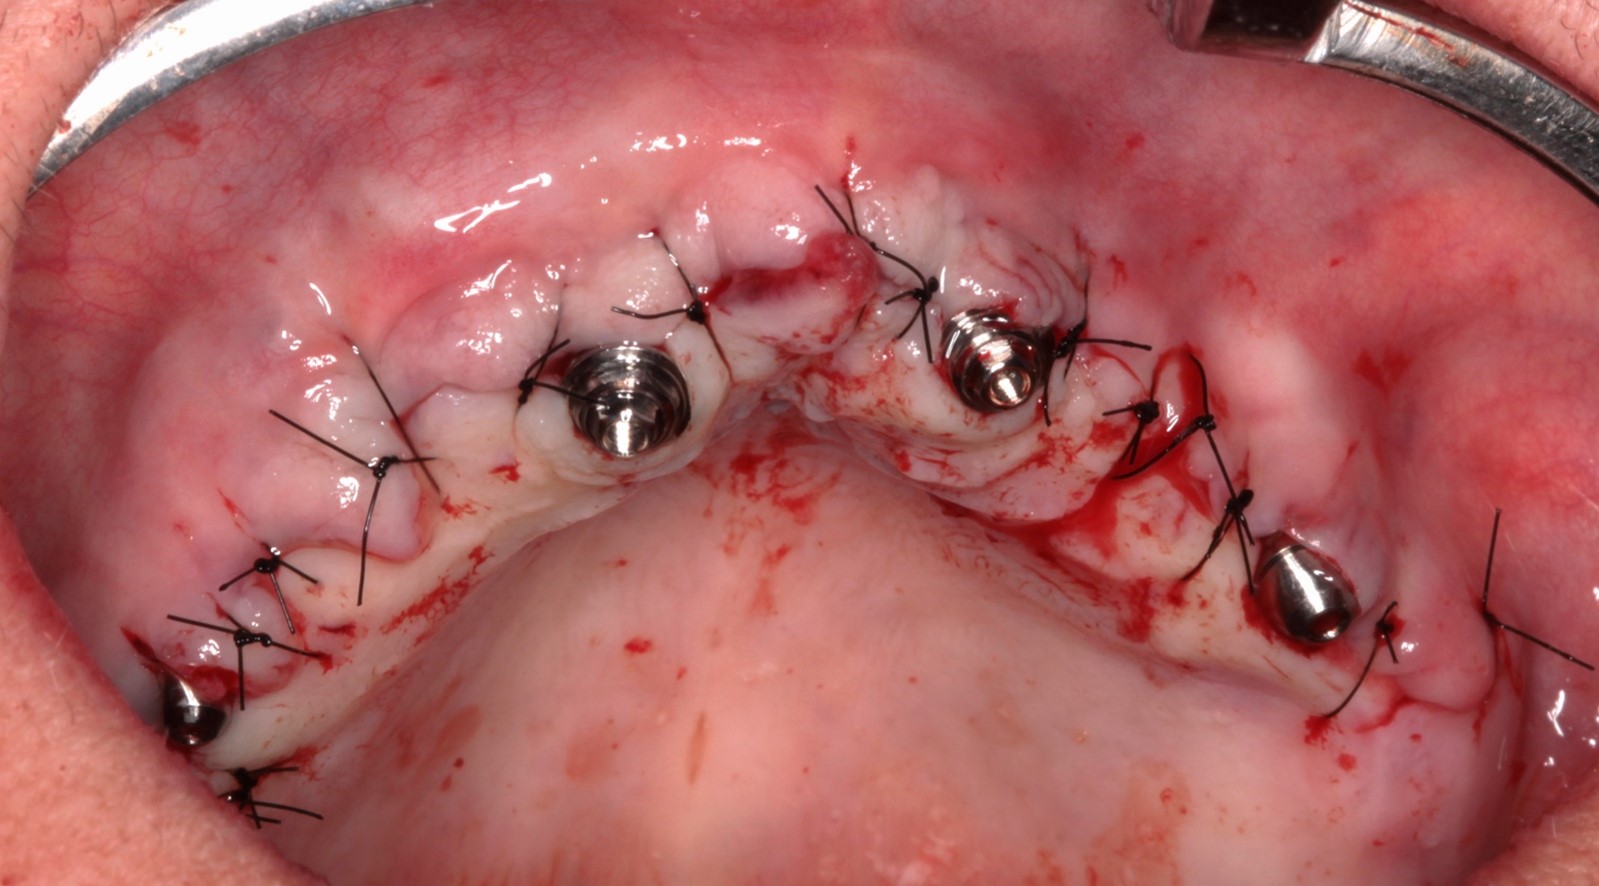

Fig. 1 e 2 – Vista oclusal

FIG. 03 – Aspecto pós-descolamento do tecido e osteotomia para regularização óssea.

FIG. 09 – Sutura simples e pós operatório imediato.